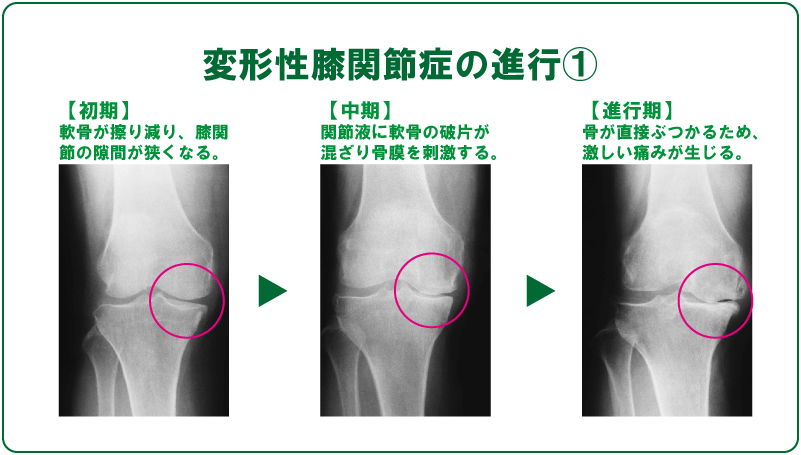

寒くなると膝が痛む